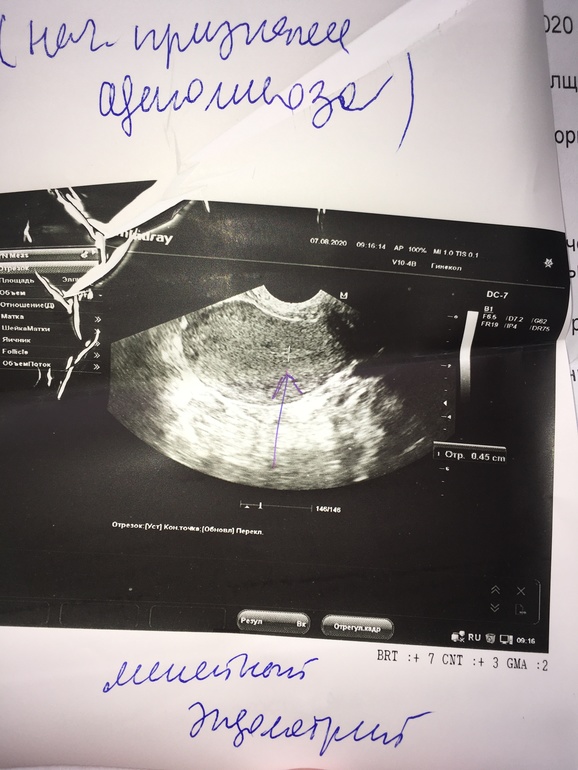

Сходила на узи , 6 дц - полипа нет 🤗кисты тоже 🤗 💃💃💃 но нашли какие-то очаги аденомиоза , такого ещё небыло 🤷♀️ Девочки , кто сталкивался ? Что за болячка такая? Мешает зачатию ? Как лечили? Приложу узи, чтоб сравнили , цикл у меня стабильный , но в этом цикле правда были болезненные месячные , но это учитывая кисту и то что было похоже на полип . Поделитесь , а то в интернете , чуть ли не рак написано.